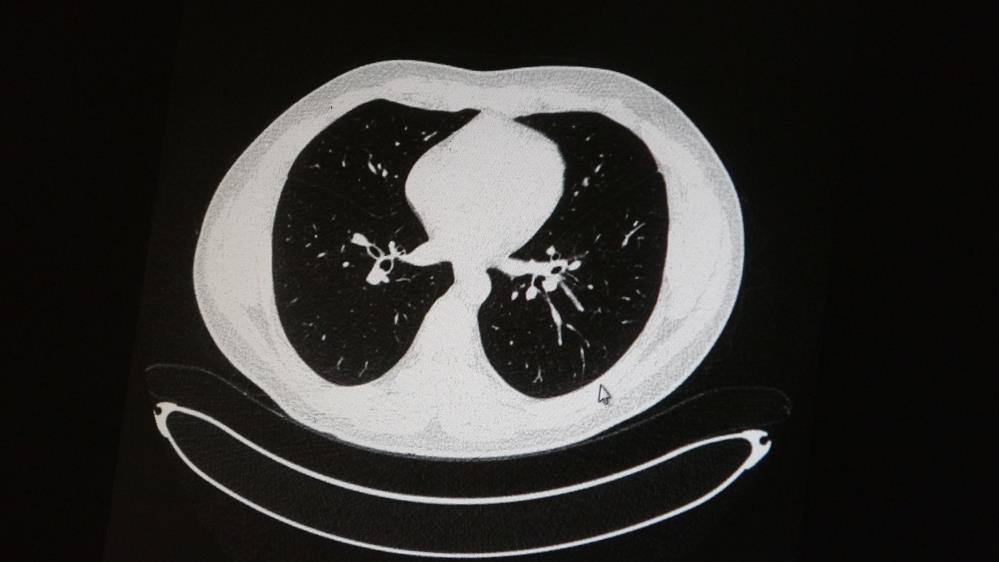

Genç olduğu halde aşı olmayanlarda hastalığın ağır seyrettiğini ifade eden Uzm. Dr. Azar, "Ben gencim, benim bağışıklık sistemim kuvvetli" diyen genç bir hastanın akciğerlerinde ciddi lekelenmelerin olduğunu ve koronavirüs zatürresi olduğunu gördüklerini belitti.

Uzm. Dr. Azar, aynı şekilde aşı olup koronavirüs hastalığına yakalanan bir başka genç hastanın akciğer tomografisinde akciğerde herhangi bir sorunun olmadığını ve hastanın durumunun iyi olduğunu gözlemlediklerini kaydetti. Uzm. Dr. Azar, sürekli şahit oldukları "Keşke biz aşı olsaydık" sözünü bir daha duymamak için herkesi aşı olmaya davet etti.

AŞI OLAN GENCİN TOMOGRAFİSİ AŞI OLMAYAN GENCİN TOMOGRAFİSİ